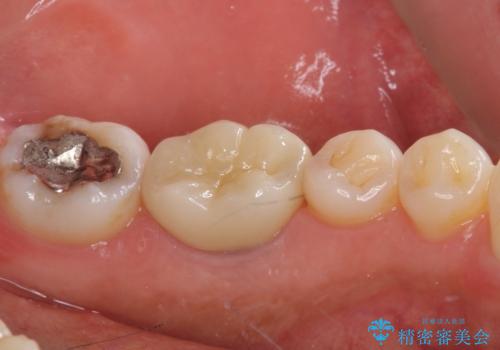

- 左下奥に、咬んだときの痛みを感じて来院された患者様です。

排膿路が形成されている歯は既に失活しており、根管治療が必要になっていました。

根管治療などを行った後に、オールセラミッククラウンにて補綴することとしました。